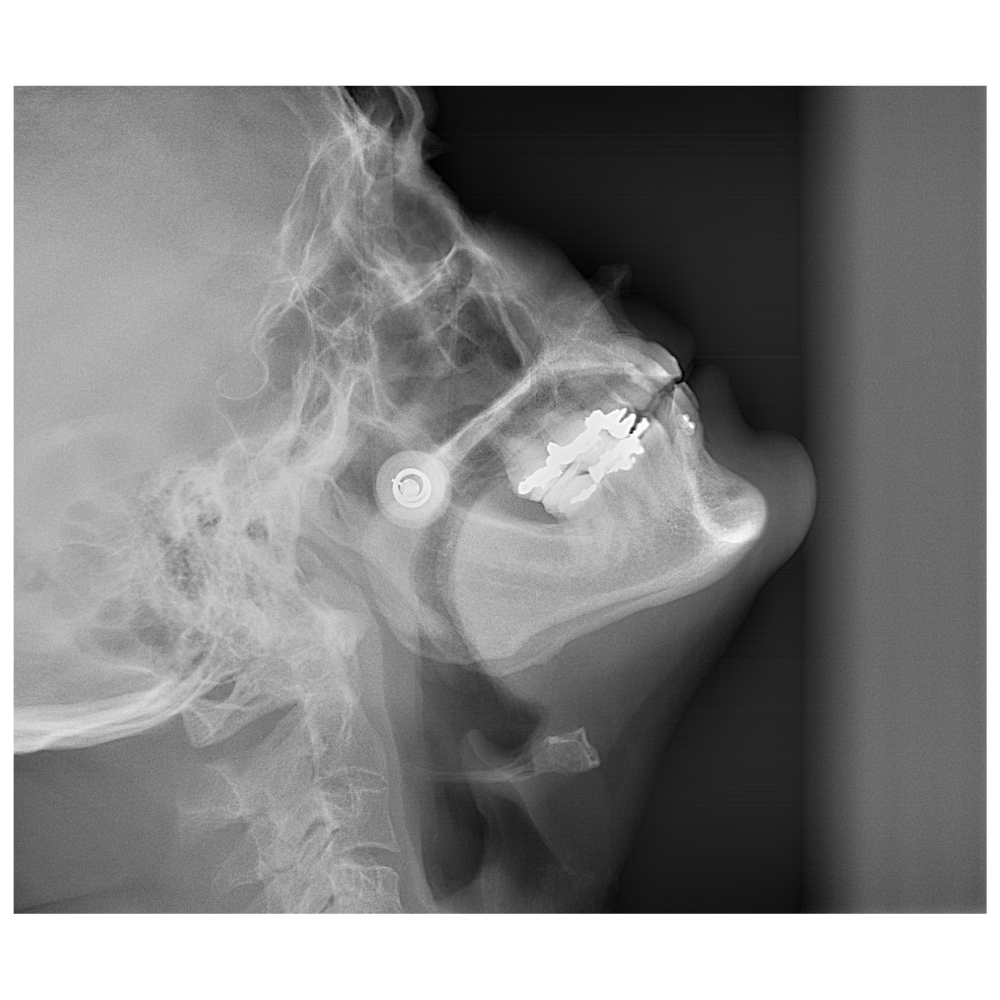

Radiografía lateral de vértebras cervicales

Análisis de la articulación temporomandibular